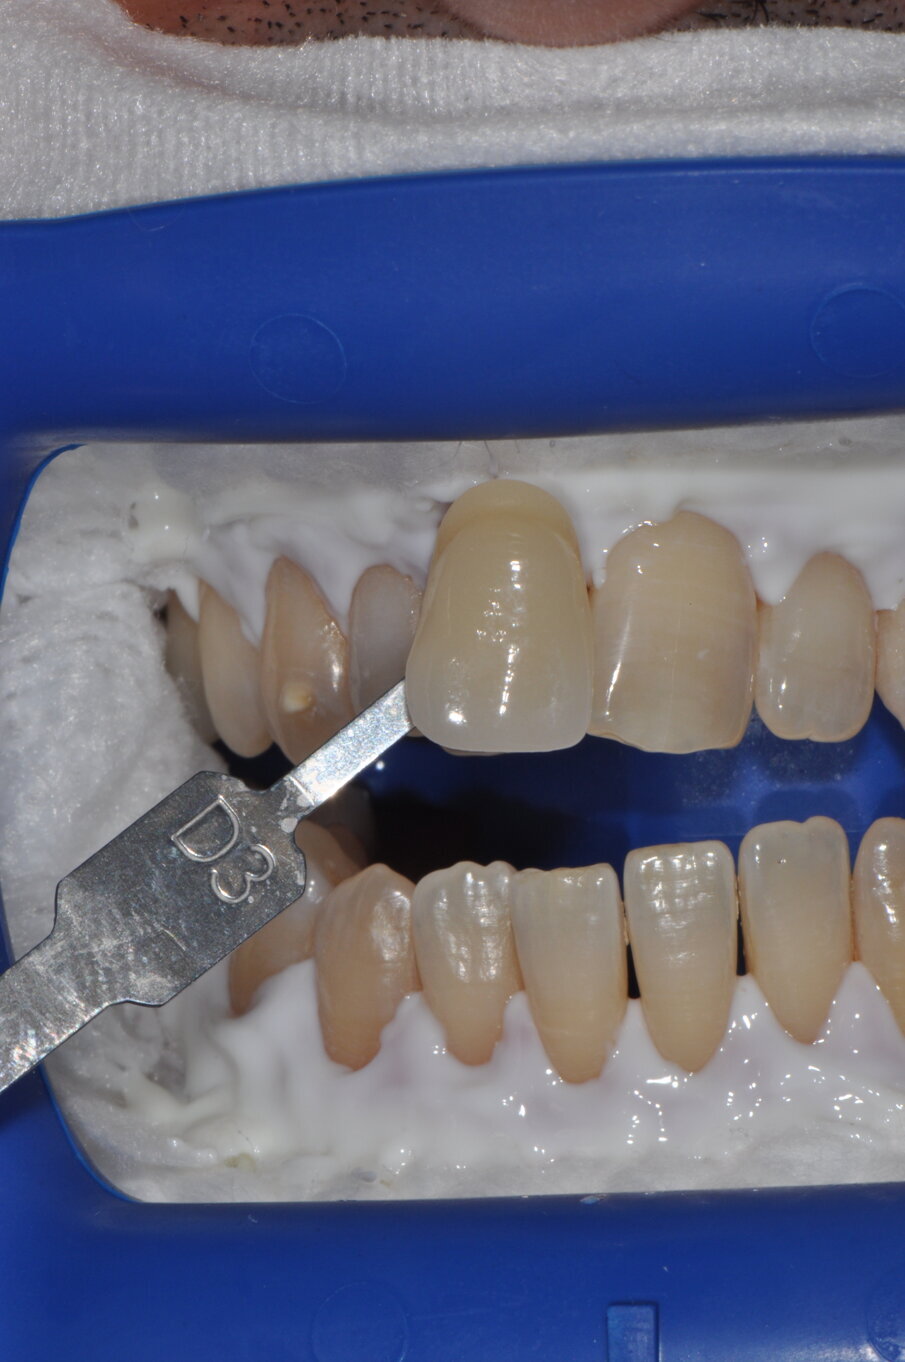

Fig. 8 - Rilevamento del colore a tempo zero utilizzando la scala “Vita” D3.

Fig. 9 - Colore post sbiancamento professionale utilizzando la scala “Vita” A2.